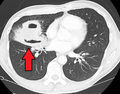

Lung abscesses are often on one side and single involving posterior segments of the upper lobes and the apical segments of the lower lobes as these areas are gravity dependent when lying down. Presence of air-fluid levels implies rupture into the bronchial tree or rarely growth of gas forming organism.